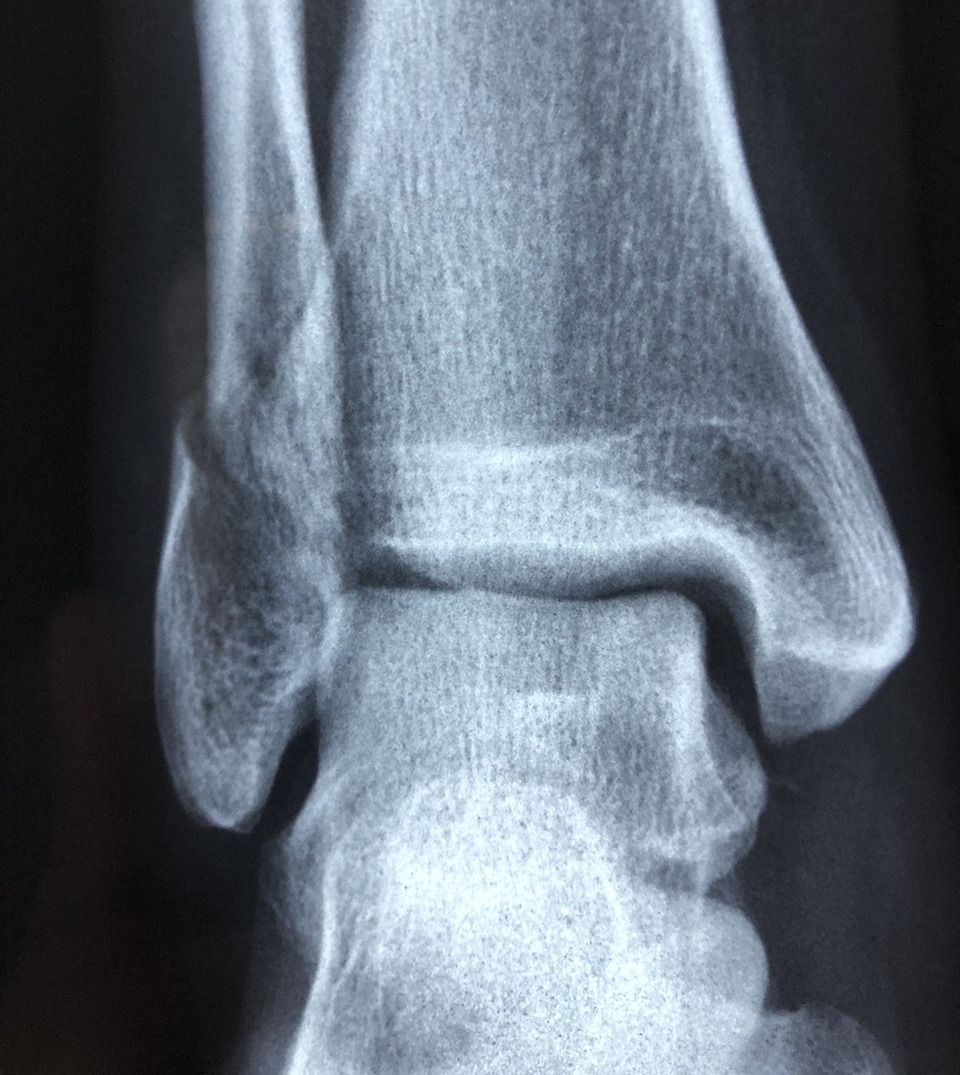

오랜만에 엑스레이도 찍어보면서 내 발목뼈모양도 구경했다.

'오른쪽 발목 염증이 심하시네요'

의사 선생님은 내 발목을 보면서 굉장히 여유롭게 말씀하셨다. 요즘 러닝이 유행하면서 비슷하게 발목이 아픈 환자가 많다고 했다. 약을 먹고 냉찜질을 하면 금방 좋아질 거라 하셨다. 덧붙여서 운동화도 잘 맞는 걸 찾아보라는 조언도 해주셨다.